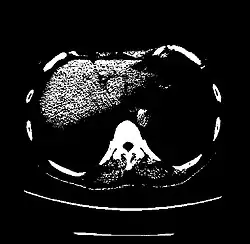

| Liver | 60 ± 6[26] | |

A practical application of this is in evaluation of tumors, where, for example, an adrenal tumor with a radiodensity of less than 10 HU is rather fatty in composition and almost certainly a benign adrenal adenoma.[31]